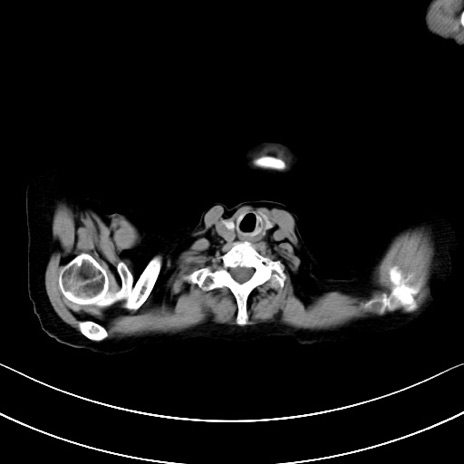

他院CT

冠状断像

矢状断像